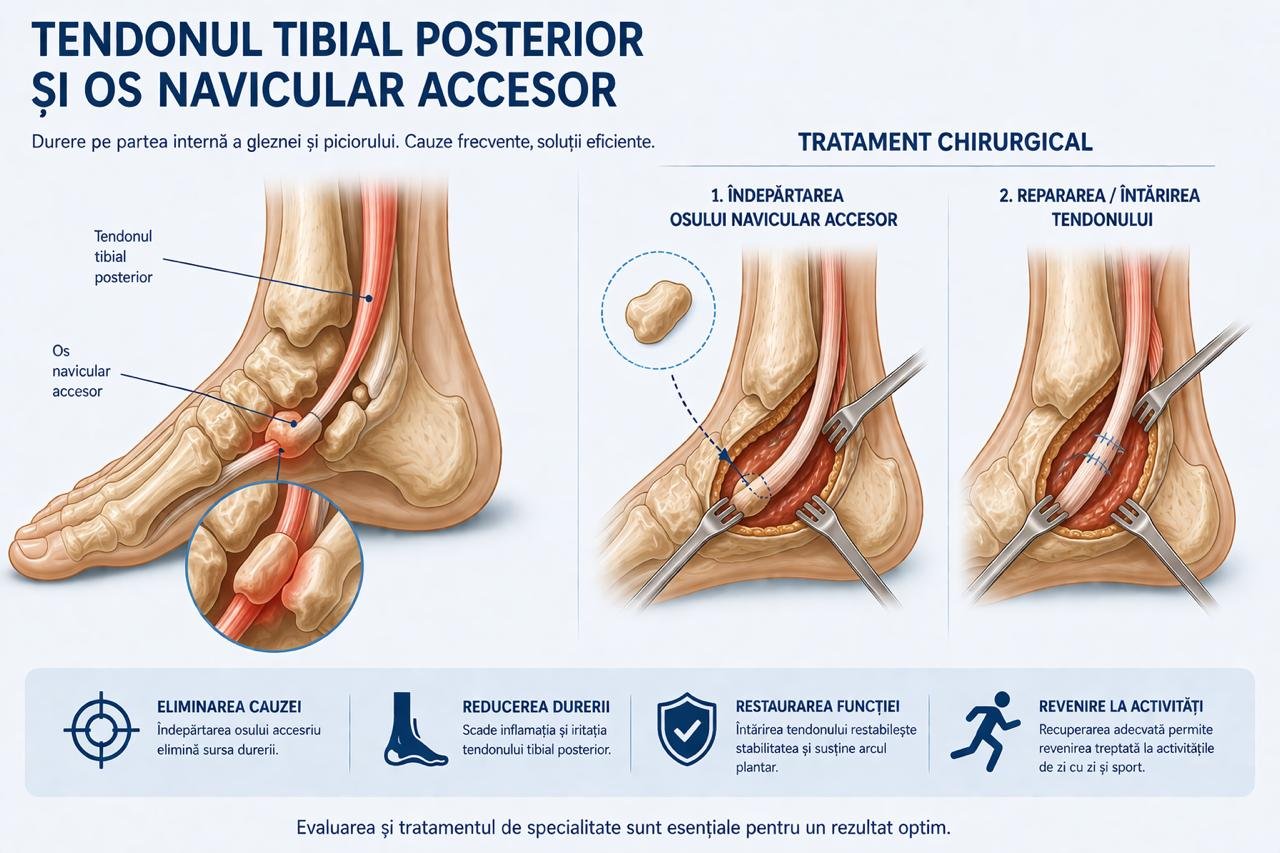

- Patologia Tendonului Tibial Posterior și Osul Navicular Accesor